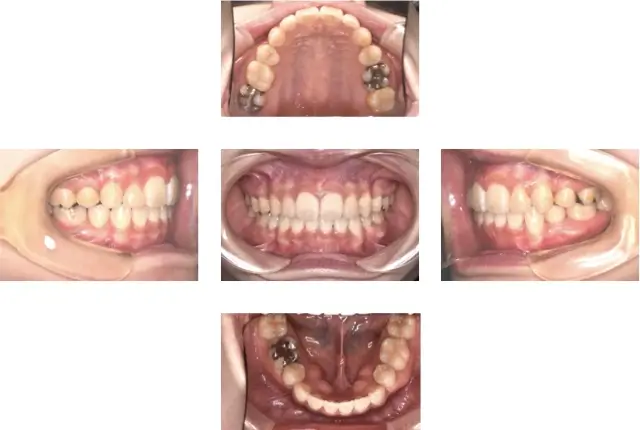

出っ歯(上顎前突)治療 1

初診時年齢 11歳6ヶ月 主訴 出っ歯が気になる

診断名 上顎前突 治療に用いた主な装置 マルチブラケット装置

抜歯部位 抜歯(上下顎左右側4番抜歯) 治療期間/回数 2年6ヶ月/30回

費用の総額 1,100,000円(税込) 費用内訳